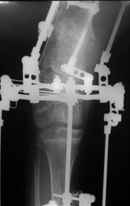

Высылаю вам фото подобной больной, у нее тоже первая попытка до меня была безуспешной.

Нужен аппарат Илизарова стабильный с множеством спиц с напайкой, временной фиксацией колена аппаратом на голени. Наверное, проще первый раз начать с бедра, остеотомию выполнить прямо на уровне перехода очага в дистальный метафиз бедра. Дистракционный остеогенез вызовет перестройку хрящевой ткани в костную. Понадобится еще пара этапов.